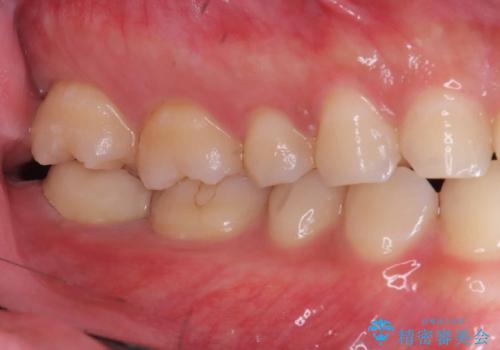

- 「銀歯を白くしたい」を主訴に来院された患者様です。

銀歯と虫歯を除去後、オールセラミッククラウンで治療を行いました。

銀歯を除去後、オールセラミッククラウンで治療を行いました。

根管治療はご希望されなかったため被せ物のみ治療しています。

クリアランスが少なかったため支台歯の真ん中に保持溝を入れています。